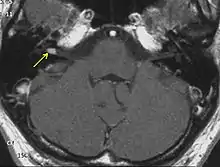

The so-called acoustic neuroma of NF2 is in fact a schwannoma of the nervus vestibularis, or vestibular schwannoma. The misnomer of acoustic neuroma is still often used. The vestibular schwannomas grow slowly at the inner entrance of the internal auditory meatus (meatus acousticus internus). They derive from the nerve sheaths of the upper part of the nervus vestibularis in the region between the central and peripheral myelin (Obersteiner-Redlich-Zone) within the area of the porus acousticus, 1 cm from the brainstem.